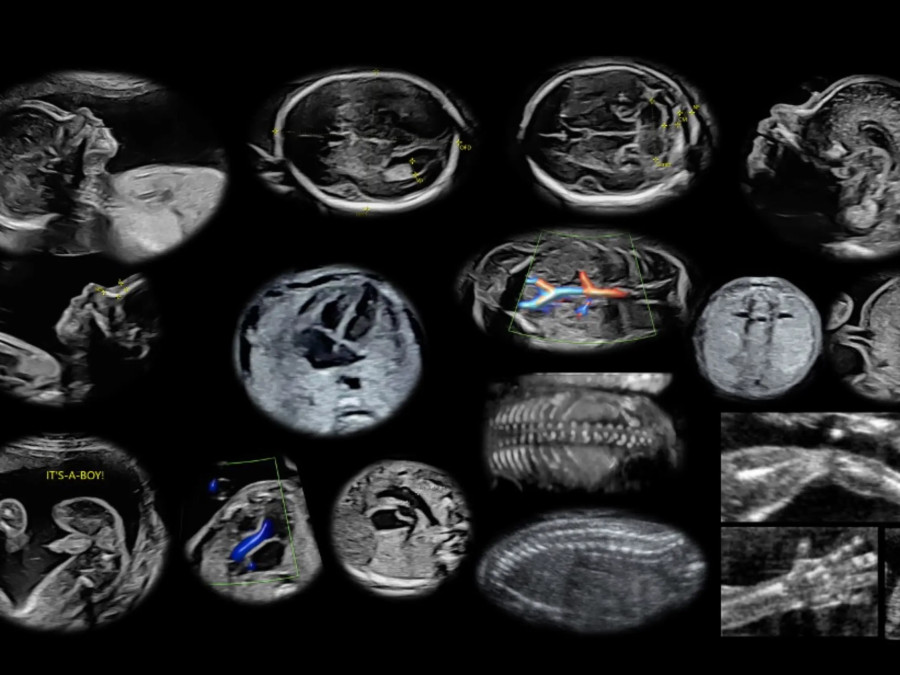

Υπερηχογραφήματα

Υπερηχογράφημα ανατομίας Β’ επιπέδου

Υπερηχογράφημα ανάπτυξης Doppler

Μέτρηση μήκους τραχήλου